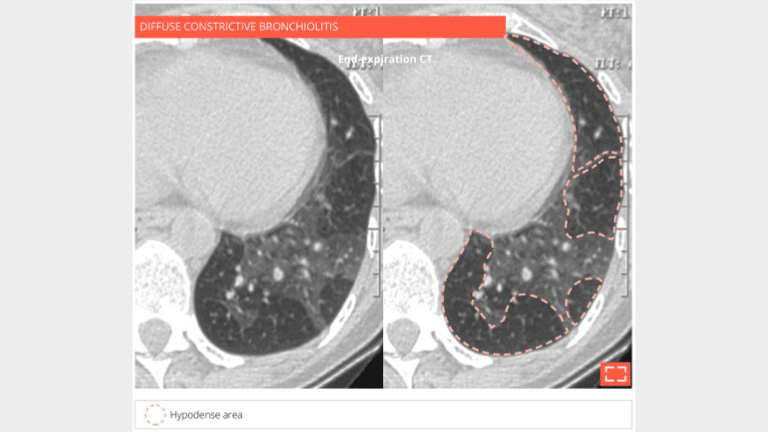

Bronchiolar mosaic attenuation

Diffuse constrictive bronchiolitis in a bone marrow transplant patient.

End-expiratory CT scan: the lung has a patchy heterogeneous mosaic attenuation alternating between normal dense areas and hypodense areas suggesting expiratory air trapping, revealing small airways disease consistent with the diagnosis of constrictive bronchiolitis.